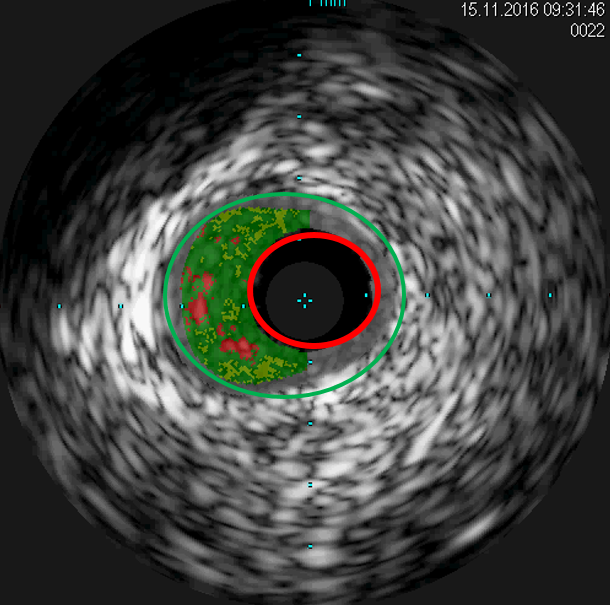

Neben den seit Langem bewährten Stents aus Metall, die lebenslang im Körper verbleiben, werden bei hierfür geeigneten Verengungen auch modernste, resorbierbare Stents (in Fachkreisen auch Scaffolds genannt) auf Magnesiumbasis eingesetzt. Sie lösen sich innerhalb eines Jahres vollständig auf und ermöglichen wieder eine natürliche Gefäßfunktion ohne dauerhaftes Fremdmaterial im behandelten Bereich. Ob eine Engstelle geeignet ist, um mit einem Magnesium Stent versorgt zu werden, wird durch den Einsatz eines Gefäßultraschalls während der Untersuchung geklärt. Eine starke Verkalkung schließt den Einsatz dieser speziellen Gefäßstütze aus.

Der Gefäßultraschall, auch IVUS genannt, zeigt zum einen den ursprünglichen Gefäßdurchmesser (grüner Kreis), zum anderen den noch durchbluteten Anteil des Gefäßes (roter Kreis).